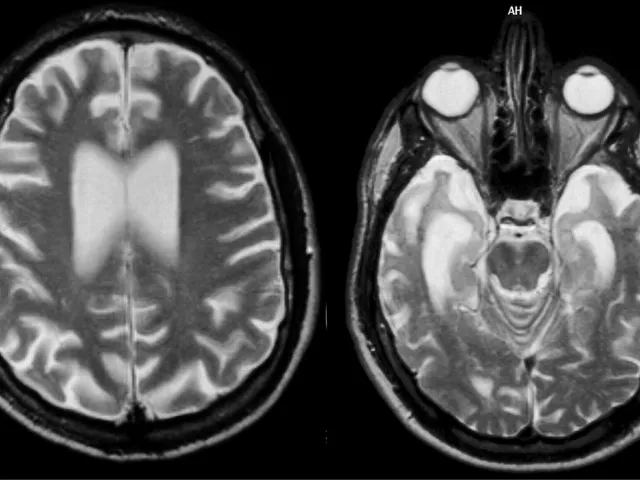

In this practical course, you will learn to read CT and MR of cognitive impairment patients in a standardised method. You will be trained to use several visual scales such as the global cortical scale and medial temporal scale and assess frontal and parietal atrophy and vascular changes that can be involved in cognitive decline. You will also learn some differential diagnoses and other entities such as Alzheimer Disease (AD) and Frontotemporal Lobe Dementia (FTLD) that can cause dementia symptoms.

Dementia can be multifactorial, and although there are some types of dementia such as AD or FTLD that can show specific regional atrophy, it is common to find a combination of several factors such as cortical atrophy and vascular changes that can contribute to the cognitive decline. AD, FTLD and other types of dementia have diagnostic clinical criteria that include the CT and the MR findings, and it is essential to do an accurate report of dementia cases to help in the early clinical diagnosis of these patients.